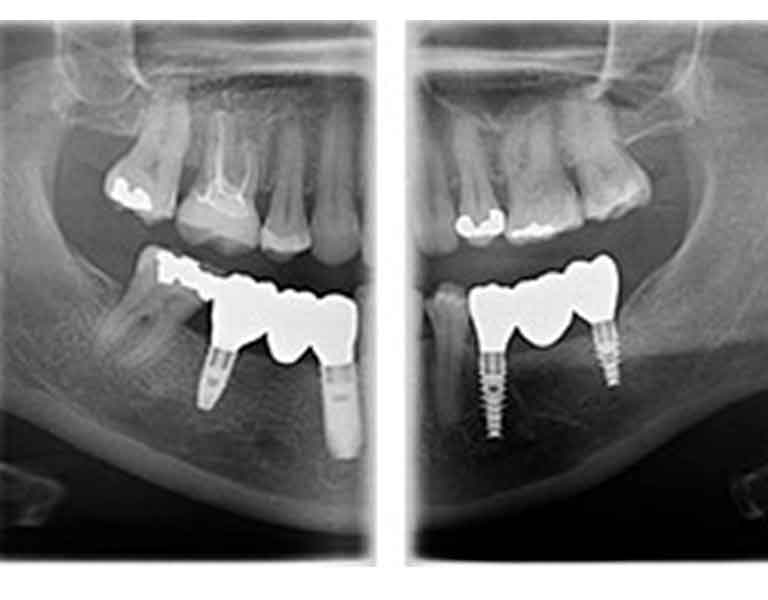

様々な場面での高解像度スキャンを実現

インプラント、歯科矯正、根管治療(根の治療)、親知らずの診断、歯周病治療など、それぞれの治療内容に最適な高解像度スキャンが可能になり、正確で迅速な診査・診断、適切な治療計画を立てることができます。

金属のアーチファクトを低減

次世代の画像向上テクノロジーにより、インプラント内部構造を見ることができ、金属によるアーチファクト(画像の乱れ)の影響を最小限に抑え、診断の精度が高まります。